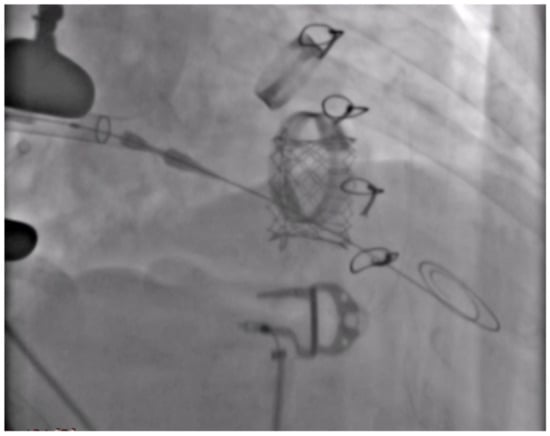

TTVIV sizing was based on the cardiac computed tomography angiography (CCTA) evaluation of the pre-existing bioprosthesis and not on the reported size of the Sorin Pericarbon bioprosthesis (Sorin Biomedica Cardio, Saluggia, Italy) because, according to Praz et al. [7], the true internal diameter of the pre-existing bioprosthesis (of interest for TTVIV) is generally 1 to 2 mm smaller than the one reported by the manufacturer (Figure 2).

In our case, the 33 mm Sorin Pericarbon bioprosthesis (Sorin Biomedica Cardio, Saluggia, Italy) proved to have a 29 mm internal diameter.

Figure 2. Cardiac computed tomography angiography measurements of the pre-existing tricuspid bioprosthesis.